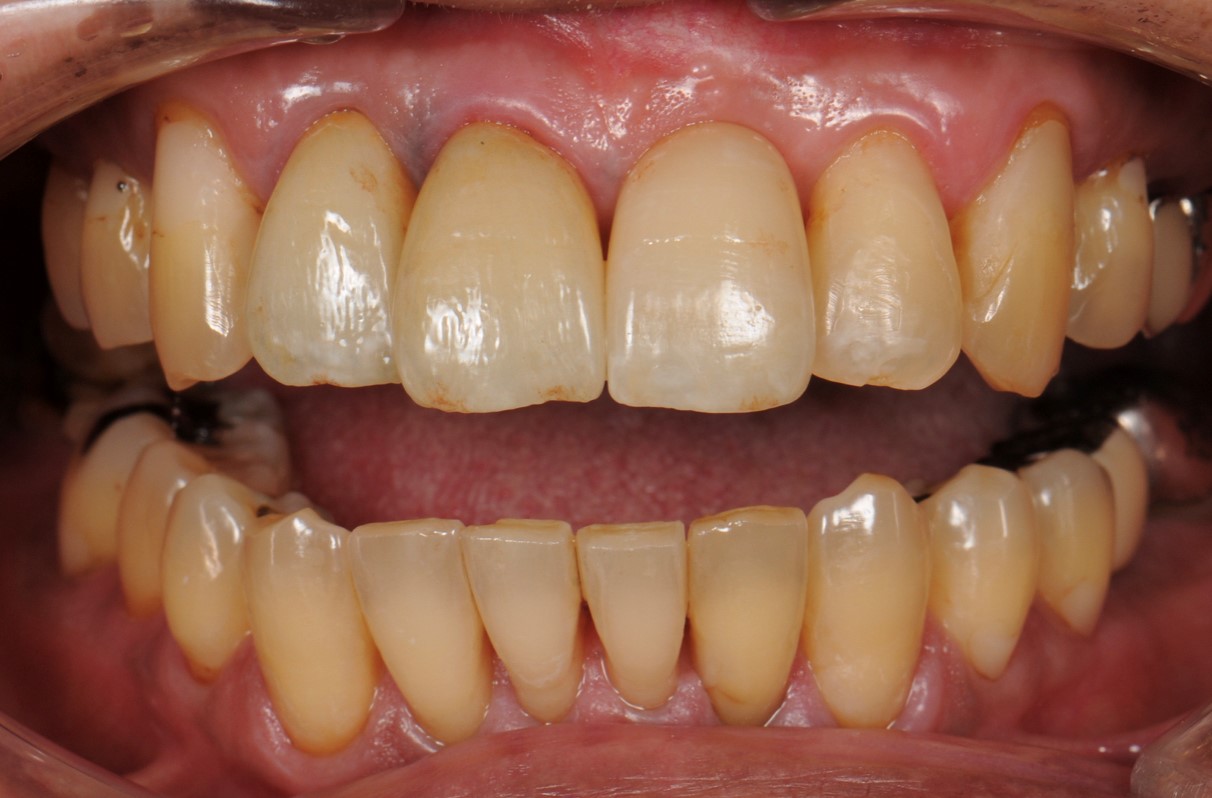

case1 症例(セラミッククラウン前歯)

治療前

| 費用(税込み) | 154,000円 |

| メリット・デメリット | デメリット 天然歯を削る必要がある。 |

| 治療回数 | 6ヵ月 |

| 主訴 | 前歯が黒い |